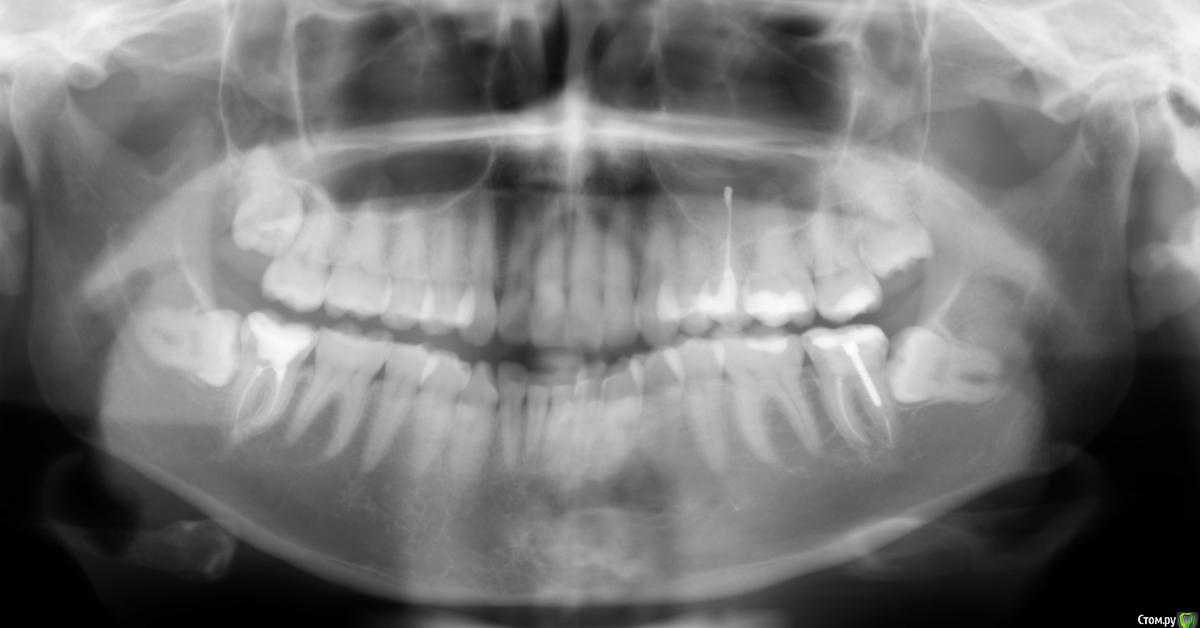

Landscape Опубликовано 30 января, 2020 Поделиться Опубликовано 30 января, 2020 Добрый день! Немного стрёмно стало после увиденного снимка, когда даже не подозревала, что такое случится. Врач сказал, что вариант сложный и обращайтесь к другим специалистам, а лучше в больницу ложиться на операцию. Обратилась к другому стоматологу хирургу, сказал, что справится со всеми засранцами (особенно с нижними, лежачими в десне) но за довольно долгое время (час-полтора). Кроме верхних, это дело минут на 10. Но терзают сомнения именно после сказанного первым врачом. Вдруг и правда случай не простой и второй хирург может ошибиться, а мне это будет стоить нервов и здоровья. Снимок прилагаю. Ссылка на комментарий

Landscape Опубликовано 30 января, 2020 Автор Поделиться Опубликовано 30 января, 2020 Вопрос в том, действительно ли случай сложный (судя по снимку) и надо обращаться в больницу или в челюстное отделение или нет? Ссылка на комментарий

red_butler Опубликовано 30 января, 2020 Поделиться Опубликовано 30 января, 2020 Вопрос в том, действительно ли случай сложный (судя по снимку) и надо обращаться в больницу или в челюстное отделение или нет?При квалифицированном удалении проблем не будет... стационар не нужен Ссылка на комментарий

Bier Опубликовано 30 января, 2020 Поделиться Опубликовано 30 января, 2020 Просто найдите врача, кто специализируется на таких удалениях. Ссылка на комментарий